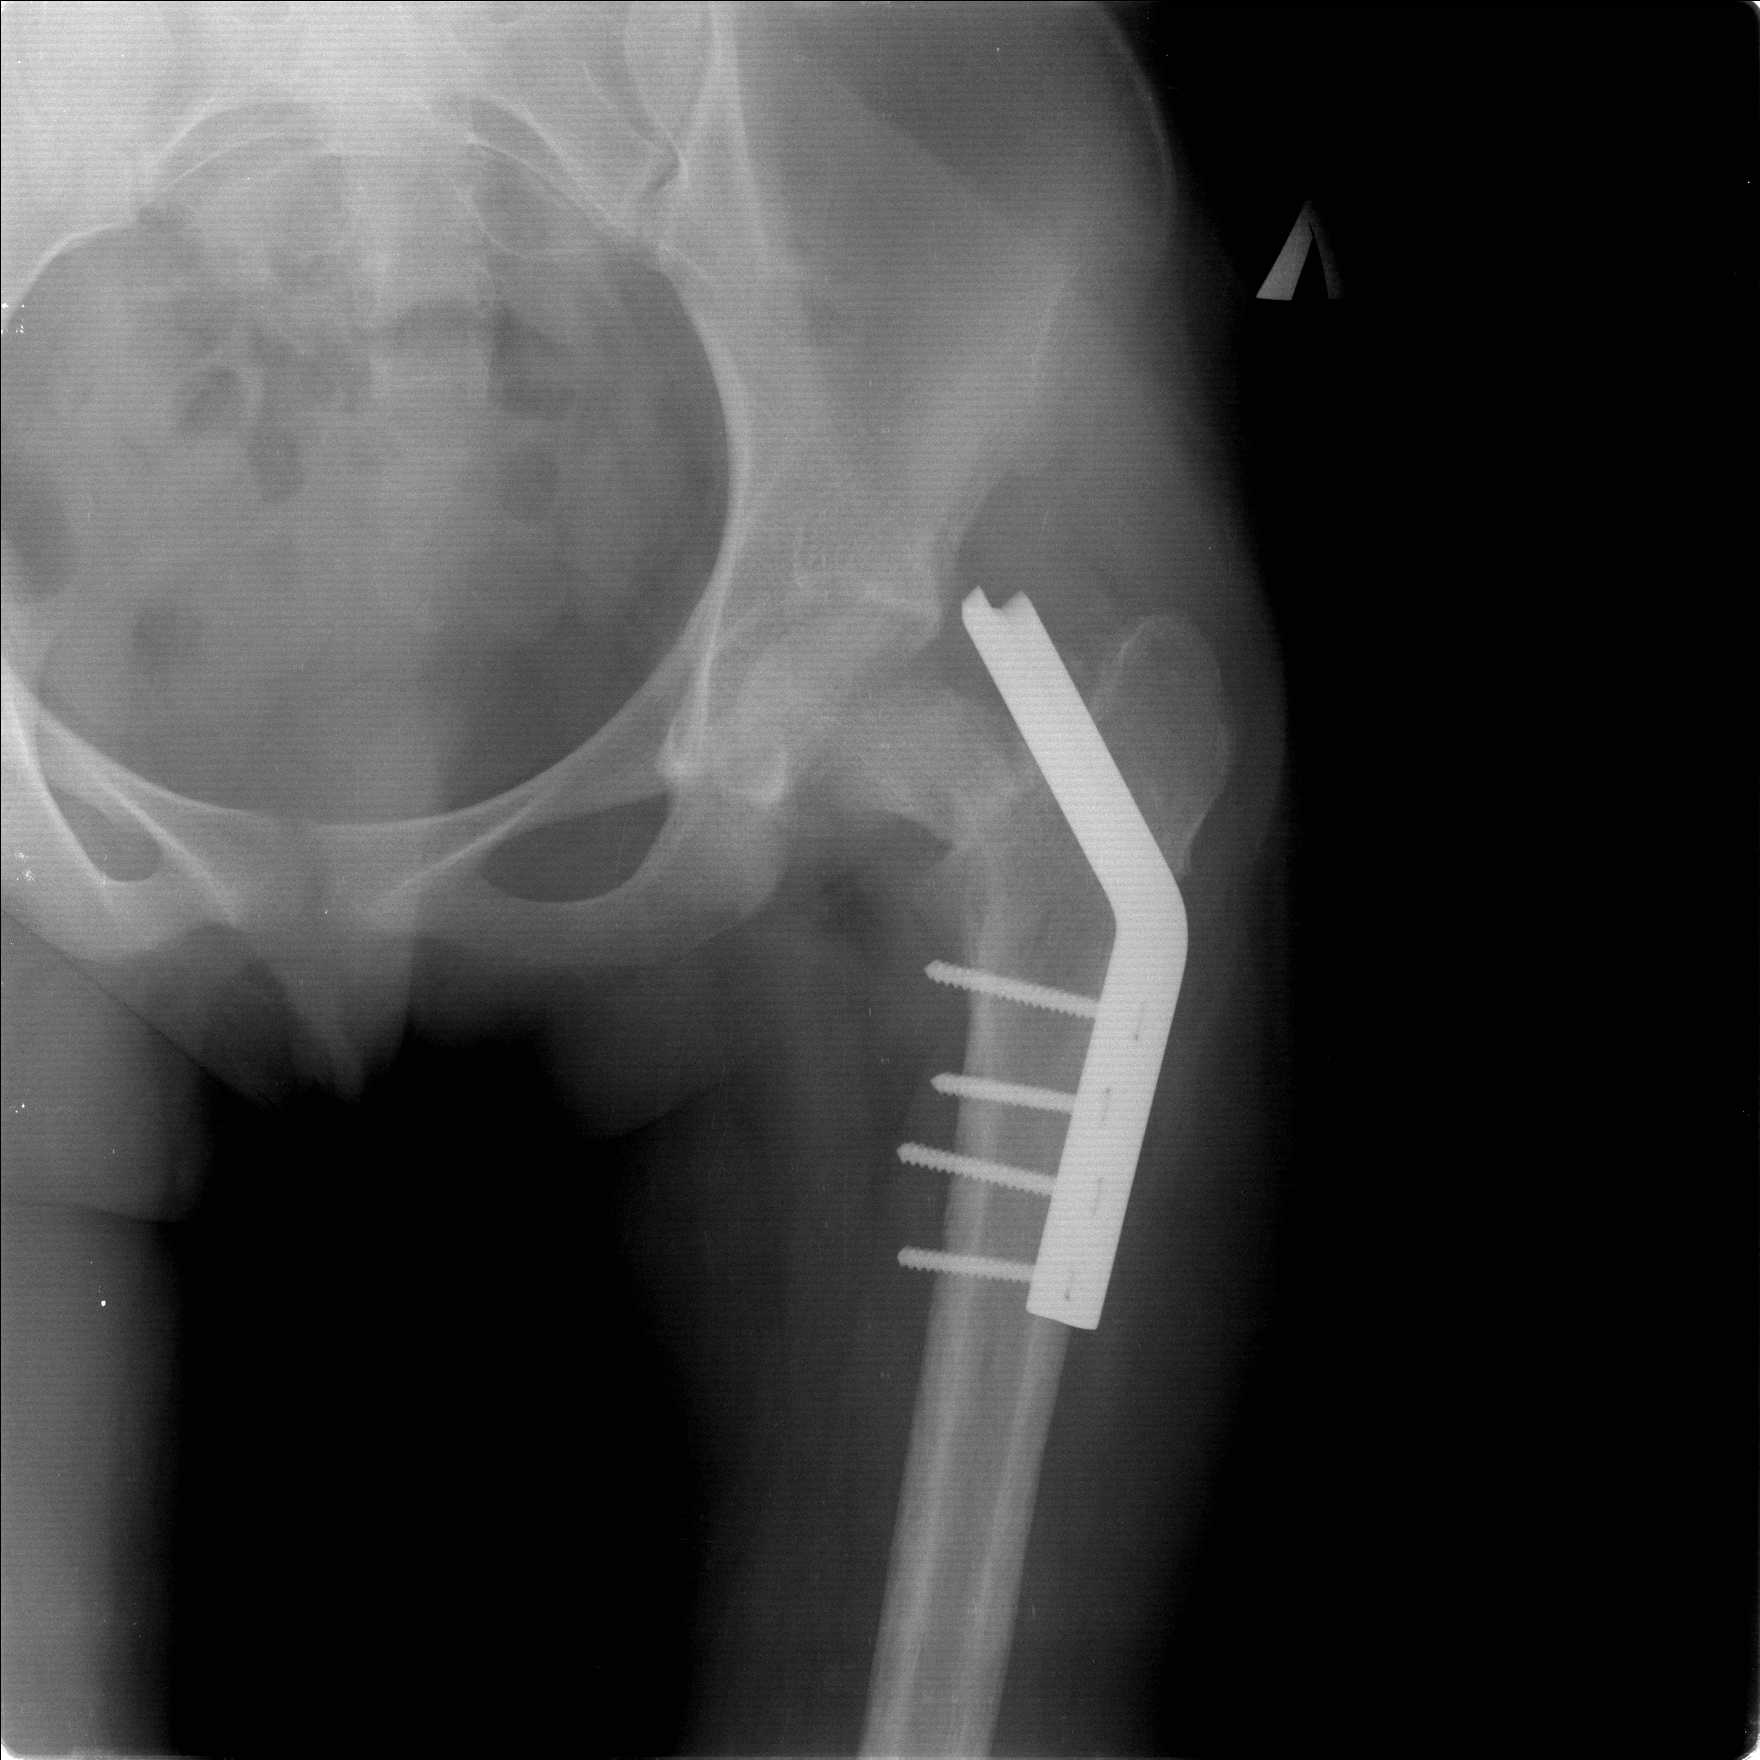

Затем переведена в наше учреждение. 18 июня выполнена операция, детали где , кто и как уточнять не имеет смысла( из протокола операции: выполнялась передняя артротомия, репозиция под визуальным контролем) . Учитывая характер выполненного остеосинтеза, после операции постельный режим 6 недель. Снимки в хронологии все выкладываю. КТ контроль сделан 2.09.16. для оценки состояния головки бедра. Помогите, определиться с дальнейшей тактикой.

Думается несколько вариантов:

1) удаление металлоконструкции, корректный реостеосинтез такой же конструкцией, похоже так же, с открытой репозицией, времени много прошло, закрыто не удасться поправить.

2) Учитывая срок может лучше удалить конструкцию, остеотомия в вертельной области ( по методике А.Н. Челнокова) и фиксация что имеем из PFN ( есть только Sanatmetal Fi-Can)

Межвертельную остеотомию оптимально было сразу и делать. Сейчас еще длина потерялась, сползло бедро проксимально. Так что да, надо делать вальгизирующую остеотомию. А перед ней - закрытую репозицию, т.е. вернуть ситуацию ближе к той, что была при поступлении.

А если удалить пластину. Затем попытаться сделать репозиции на тракционном столе или аппаратом таз бедро. Фиксировать спицами под ЭОП и последующем фиксировать DHS-конструкцией .

А сейчас - после неудачной попытки открыто лечить уже несращение и варусную деформацию? Для просто остеосинтеза условия в зоне стыка уже хуже . Сейчас закрыто надо хоть как-то получить длину. А шеечно-диафизарный угол с небольшой гиперкоррекцией - за счет остеотомии. Которая и линию перелома переориентирует ближе к горизонтальной, т.е. больше на компрессию. И еще и medicata, т.е. будет способствовать улучшению кровоснабжения в этой области.

согласен с Александром Николаевичем, надо пытаться сохранить сустав (в т.ч. его страдающее кровоснабжение. Судя по КТ Сохраняется ретроверсия шейки бедра. Вероятны трудности с репозицией последней. Для создания правильного направления шеечных винтов (Винта) возможно придется делать вальгусно-антекурвационную межвертельную остетомию, тем самым произвести разгибание в т/бедренном суставе проксимального отломка. И ретроверсия станет в большей степени вальгусом. То есть точка входа для гвоздя должна быть кзади от торчащей части прорезавшегося клинка со всеми вытекающими перемещениями проксимальной части.